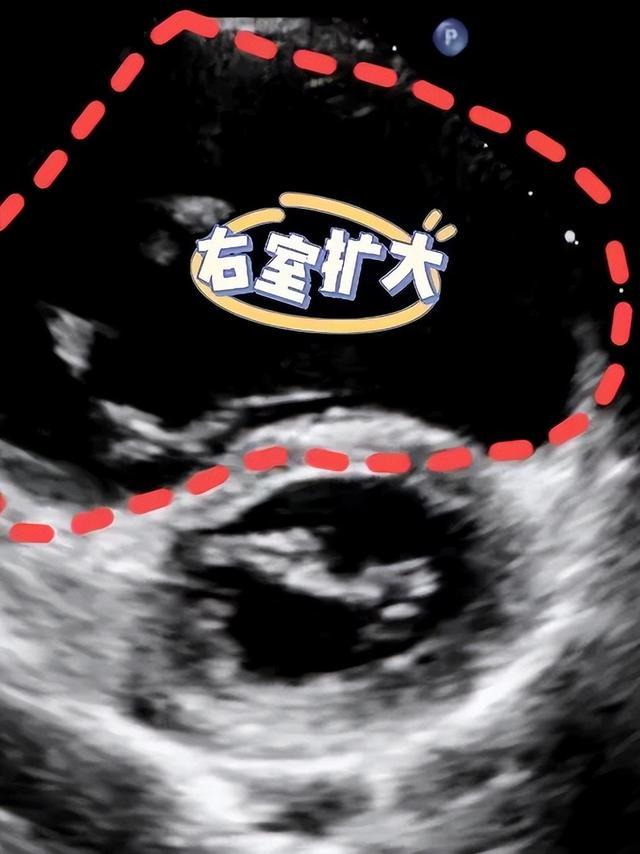

例如,心脏彩超主要检查房子(心房/室)是否增大,墙壁(房/室壁)是否增厚,墙壁是否出现孔洞(房/室缺),门窗(房室瓣、半月瓣)是否关闭良好,以及房子的稳固情况(心功能)等。

右心室扩大